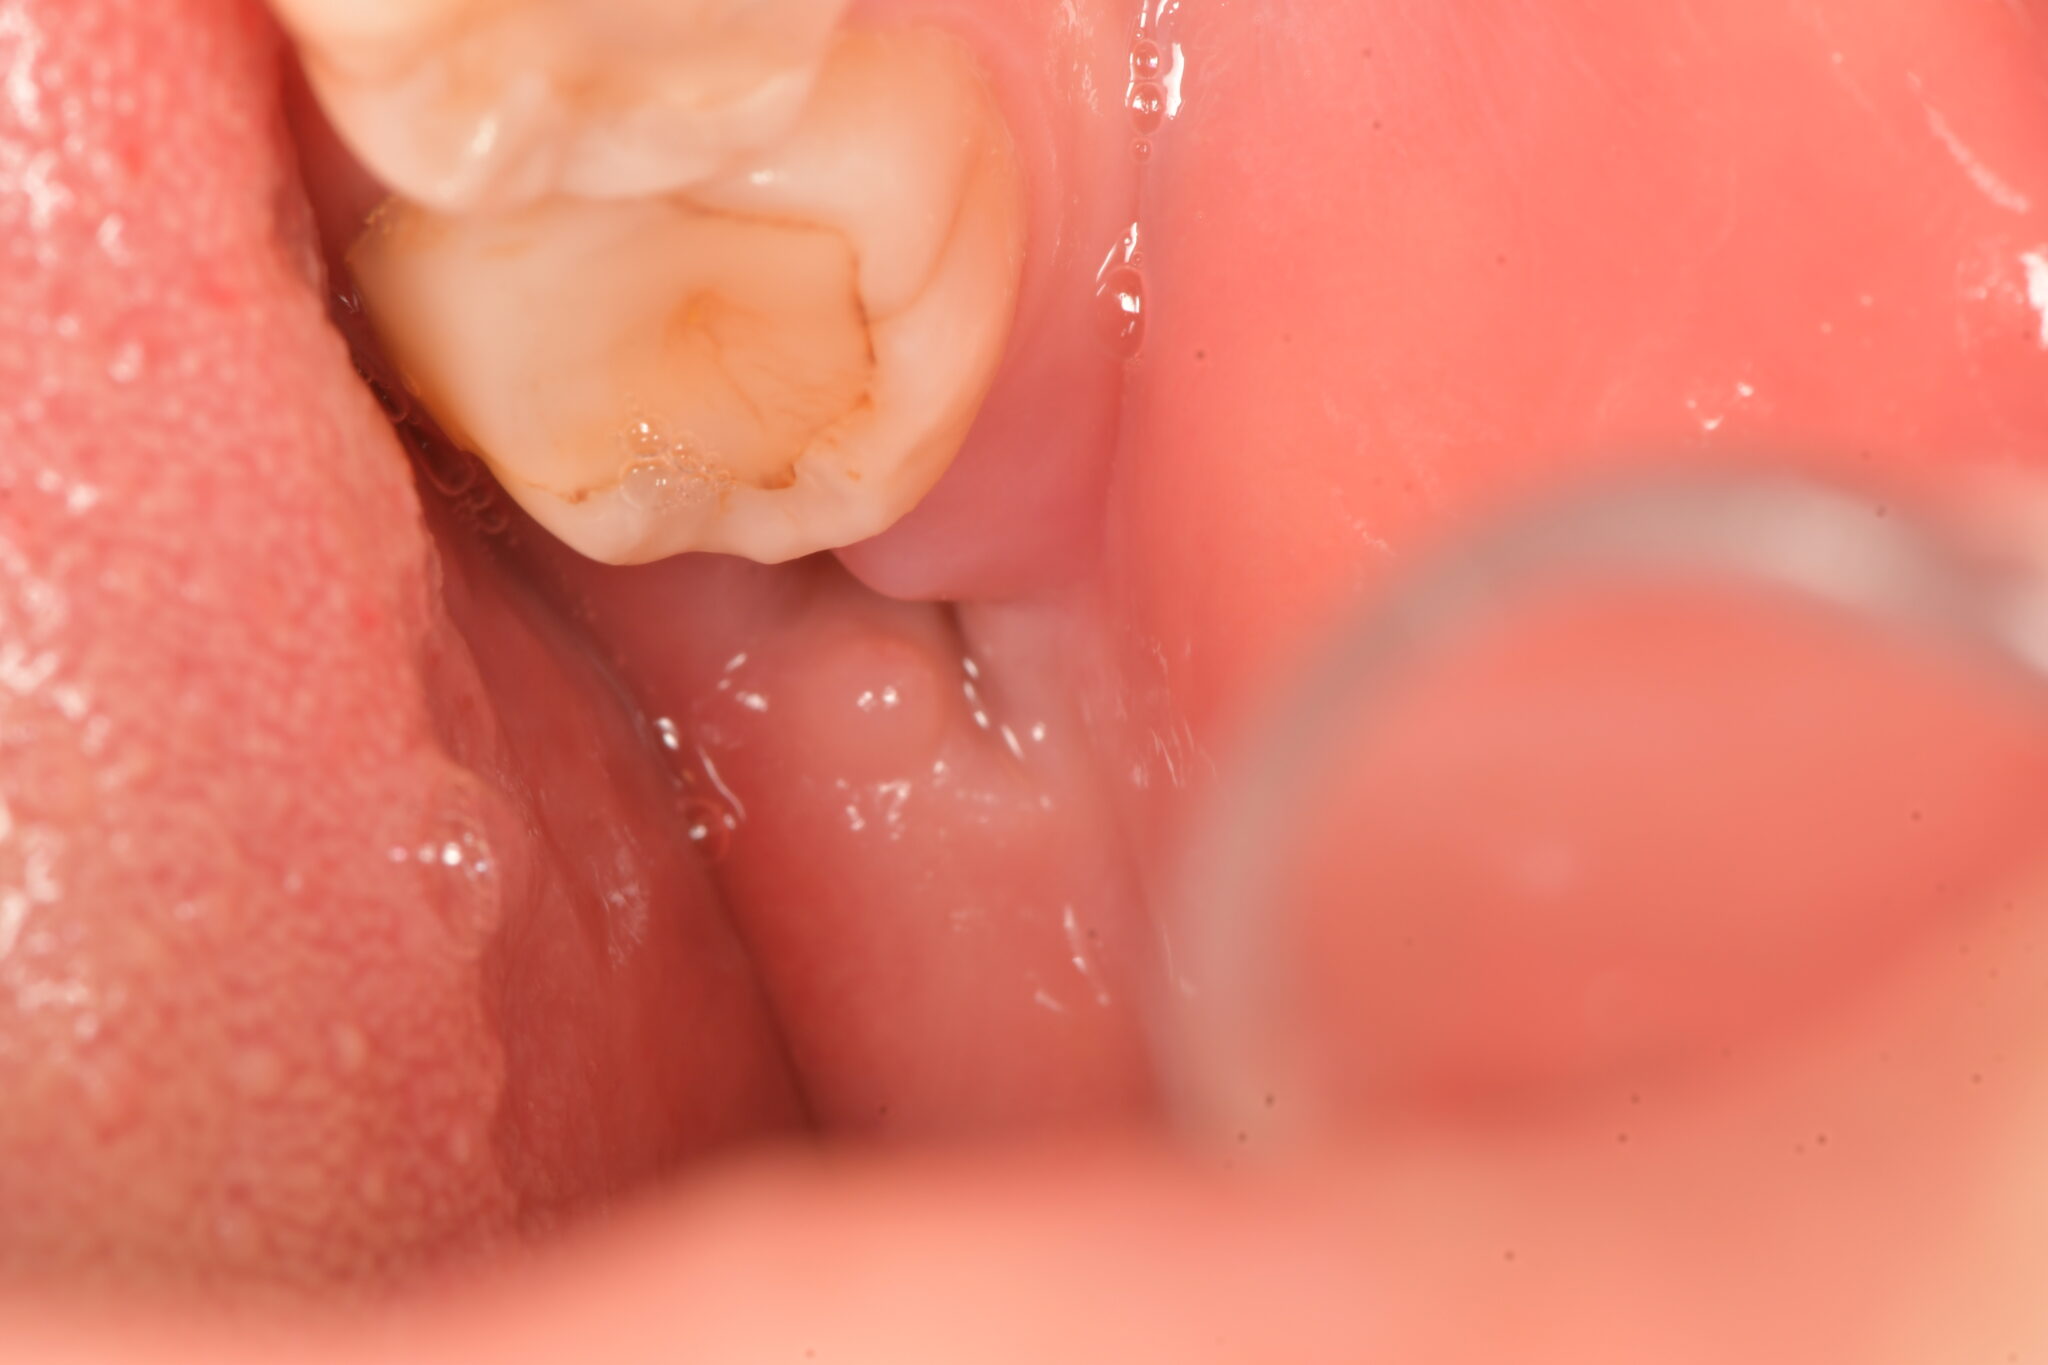

場合によっては、親知らずが正しい位置に移動するための十分なスペースが口内にない場合があります。歯肉を斜めに突き破ったり、部分的にしか突き抜けなかったりすることがあります。これが発生すると、 埋伏親知らずと呼ばれ、痛みや感染症などの問題を引き起こす可能性があります。

歯が歯茎の途中までしか生えていない場合、食べ物が歯と歯茎の間に挟まりやすくなります。また、これらの歯を清潔に保つことが難しくなり、感染症や虫歯につながる可能性があります。

ただし、親知らずが歯茎を完全に突き抜けて生えている場合でも、問題が発生する可能性があります。斜めに生えていると、口の中や歯茎をこすってしまう可能性があります。他の歯を押して痛みを引き起こす場合があります。

口の中に歯を入れる十分なスペースがない場合、親知らずの抜歯手術が必要になる場合があります。歯が影響を受け、感染が促進される可能性があります。斜めに生えた親知らずは痛みを感じることがあります。